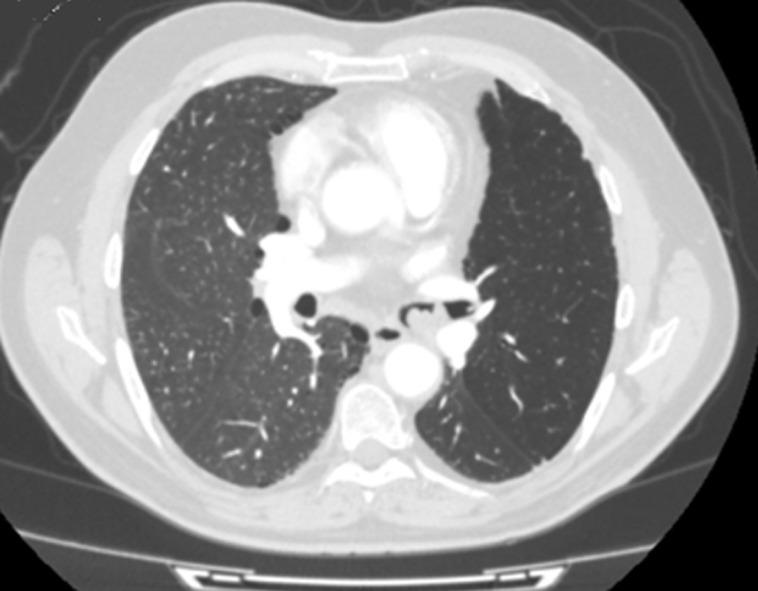

Bronchopulmonary cancer is the leading cause of death in men and the second in women. Some endoscopic or radiological features may guide histological diagnosis and thus facilitate therapeutic management. We here report the case of a 54-year old man, with a history of smoking and recent coronary stent implantation, presenting with haemoptysis and worsening of dyspnea which had evolved over the last month. Chest x-ray showed left pulmonary hemifield lucency with signs of retraction. Bronchial fibroscopy objectified raspberry bud formation spontaneously bleeding, originating from the left main bronchus and suggesting carcinoid tumor. Chest computed tomography (CT) scan showed poorly enhanced endoluminal tissue process at the level of the left main bronchus, located four cm from the carina and complicated with atelectasis. Diagnostic and therapeutic surgery helped to adjust to a diagnosis of endobronchial amartocondroma.

支气管肺癌是男性死亡的主要原因,在女性中排第二位。一些内镜或放射学特征可能有助于组织学诊断,从而便于治疗管理。我们在此报告一例54岁男性病例,有吸烟史且近期植入冠状动脉支架,出现咯血和呼吸困难加重,症状在过去一个月内逐渐发展。胸部X线显示左肺野透亮,有回缩迹象。支气管纤维镜检查发现有源自左主支气管的呈覆盆子芽状形成且自发出血的病变,提示类癌肿瘤。胸部计算机断层扫描(CT)显示左主支气管水平腔内组织强化不佳,距隆突4厘米,并发肺不张。诊断性和治疗性手术有助于确诊为支气管内错构瘤。